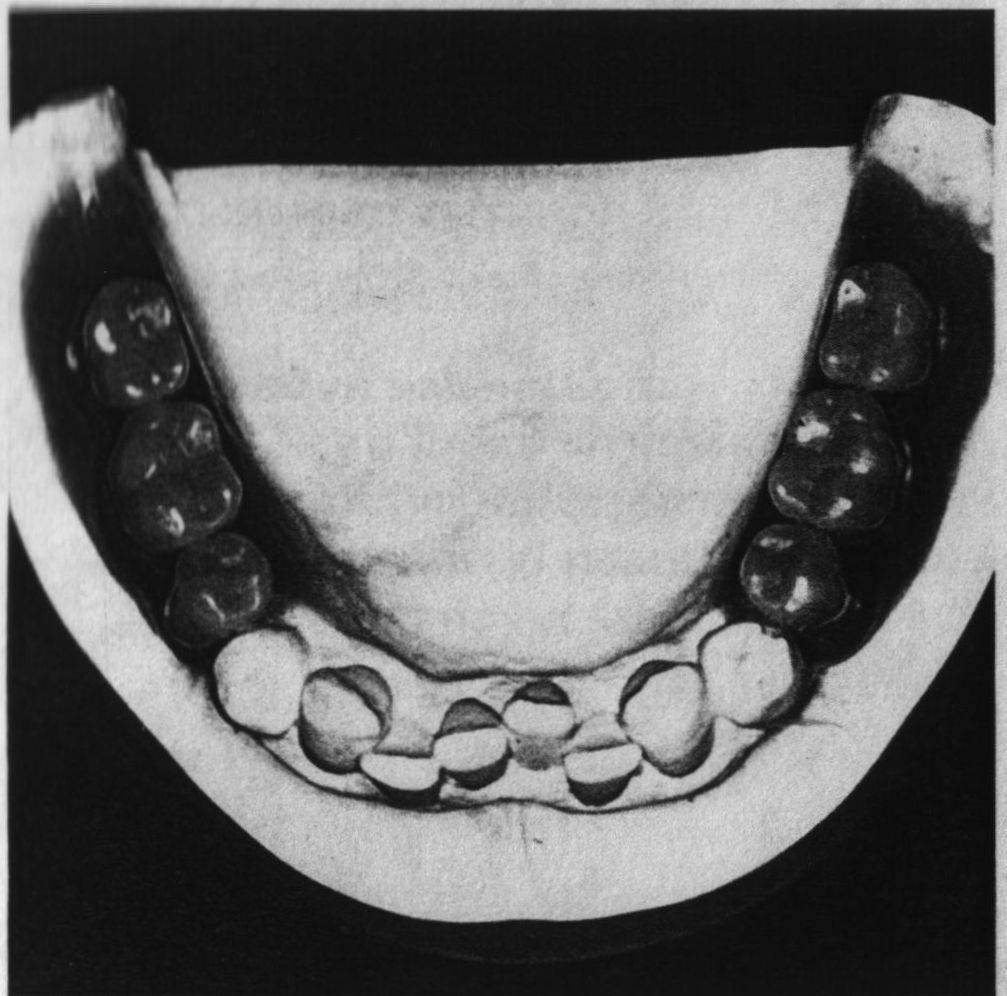

Формы промежуточной части nмостовидного протеза:

1 – касательная для передних зубов

2 – висячая при высоких клинических nкоронках зубов

3 – висячая при низких клинических nкоронках зубов

4 – седловидная цельнометаллическая

5,6 – висячая с облицовкой губной nили губно-жевательной поверхности

7 – седловидная с облицовкой видимых nповерхностей – жевательной и частично боковых искусственных зубов нижней nчелюсти.